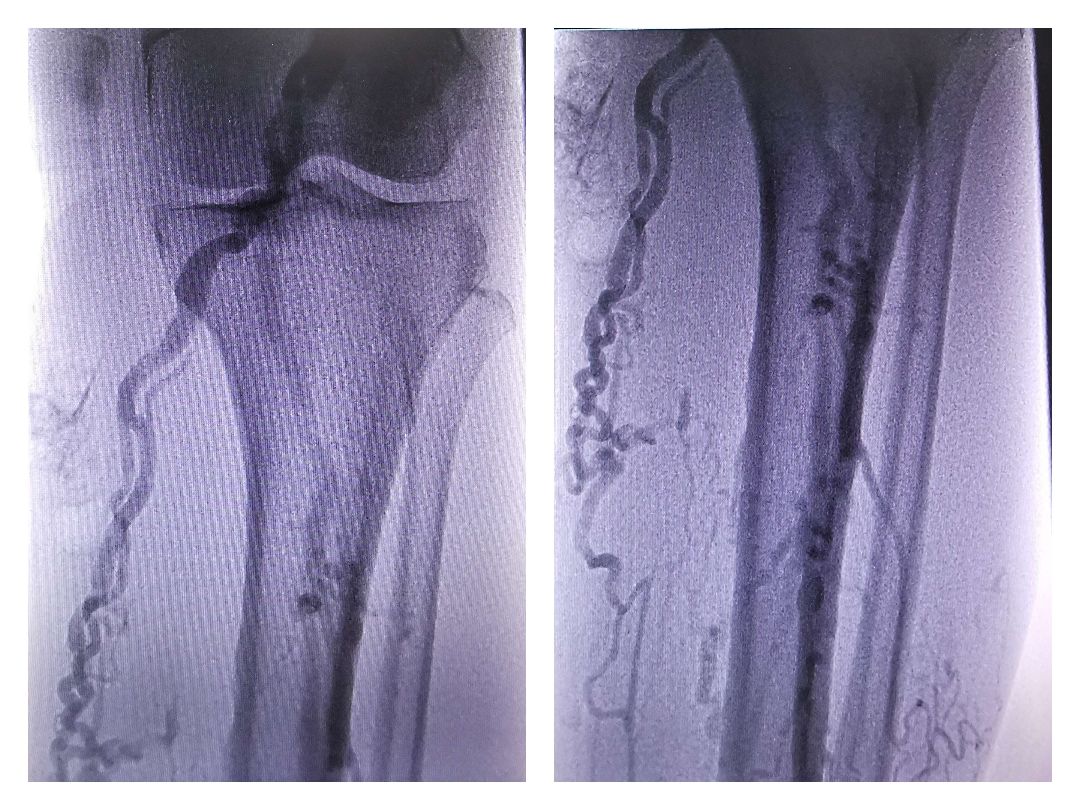

只有抓住静脉曲张的形成根源,才能彻底解决静脉曲张问题,静脉曲张是因为静脉掰膜长期受到压力的影响,导致静脉掰膜失去功能机制,静脉血液倒流增加静脉血管压力,造成静脉管壁扩张延伸,在腿部形成静脉突起。因此想要解决静脉曲张问题,就要修复受损静脉,恢复静脉掰膜功能机制。

健康开心生活:而对于人情世故方面,方鸿渐感到的应该是悲哀吧,从感慨时的李梅亭,再到苏文纨的转变,尤其是在三闾大学的那一段时间,高松年的老谋深算,陆子潇的刻薄呆板,韩学愈的虚伪做作,刘东方的阴险狡诈,汪处厚则是虚伪、道貌岸然的伪君子,而董斜川、诸慎明则更是墙头之草。他深切地体味到了人情冷暖,势力相对,那些近乎滑稽的言行,让我们大笑的同时,更让我们愤恨、咬牙切齿。方鸿渐看透了,离开了。而他能够和赵辛楣成为朋友,也似乎只是赵辛楣对他的怜悯罢了。静脉曲张虽不直接危及生命,但却严重影响美观,给无数患者带来极大的痛苦及心理障碍,给原本富贵的人生地位和幸福的家庭带来隔膜与偏见,故又有“美腿杀手”的称号。为了让自己的静脉曲张病情尽快好转,让腿上的的蚯蚓尽快消失,好在夏季像正常人一样穿夏装。静脉曲张患者应积极行动起来。下肢静脉曲张吃什么中药,到底用什么方法来治疗静脉曲张呢?脉活治疗静脉曲张案例分析没病一身轻,得了病的话就做什么都没心情了,就连出去逛街的心情都没有,特别的得了静脉曲张,不光是心情问题,是都没有自信再出门了。

不治好这个病,我都真的不敢出门了,都害怕别人用一样的眼光看我。即使穿了长点的裤子,但还是生怕别人看到自己的腿。正因为这样,我还没有找到男朋友,他们都说可能不适合,我也知道,毕竟现在的我可能真的是都没有顾及到自己的交友方面。本来自己也没打算想找的。以为“高手是孤独的”这样才能一心一意地赚钱。没想到的事情发生了。一向追求完美的我,也有了不完美的地方,我的腿部开始发生病变了,我早就知道它疼,但是没有太顾及,不就是疼点嘛,没有什么的,我是个强人,怎么能向这点的疼痛低头呢?我就没有再管过自己的腿我发现自己的腿上可能真的有点不正常,我去医院想做下检查,医生告诉我说我的是静脉曲张的症状,如果不治疗的话可能腿部就会变得很难看了。他还给我看了不少的病例,不过我没看几个就不看了,我可不想自己的腿变成那个样子,真是那样的话我连穿漂亮衣服的自信都没有了,肯定是不行的,我开始发动身边的所有朋友帮我找找看看有没有人找到这样的药。脉活专家提醒:轻微下肢静脉曲张一般不需要治疗,预防和保健是最重要的,但是如果静脉曲张症状没有缓解,且有加重趋势,患者一定要及时诊断治疗,夏季气温升高,人体全身循环系统运转也在逐渐加快。

寒春时节如果已经出现静脉曲张发病,导致血液静脉膜瓣功能破坏,由于静脉曲张又是不可逆的疾病,夏季血液流通加快,则很容易发现下肢血管症状,例如下肢血管明显,出现结节,或者伴有小腿刺痛感等。加上夏季穿着变少,更加便于发现小腿上的血管症状表现,及时的发现病情。注意!!!在静脉曲张治疗上,冬春季节由于气温偏低,很多静脉曲张患者保暖不足容易加重病情,加上病情容易高发,所以治疗起来较为麻烦,而现在气温上升此时是静脉曲张治疗的最佳时机,千万不要错过而对于人情世故方面,方鸿渐感到的应该是悲哀吧,从感慨时的李梅亭,再到苏文纨的转变,尤其是在三闾大学的那一段时间,高松年的老谋深算,陆子潇的刻薄呆板,韩学愈的虚伪做作,刘东方的阴险狡诈,汪处厚则是虚伪、道貌岸然的伪君子,而董斜川、诸慎明则更是墙头之草。他深切地体味到了人情冷暖,势力相对,那些近乎滑稽的言行,让我们大笑的同时,更让我们愤恨、咬牙切齿。方鸿渐看透了,离开了。而他能够和赵辛楣成为朋友,也似乎只是赵辛楣对他的怜悯罢了。